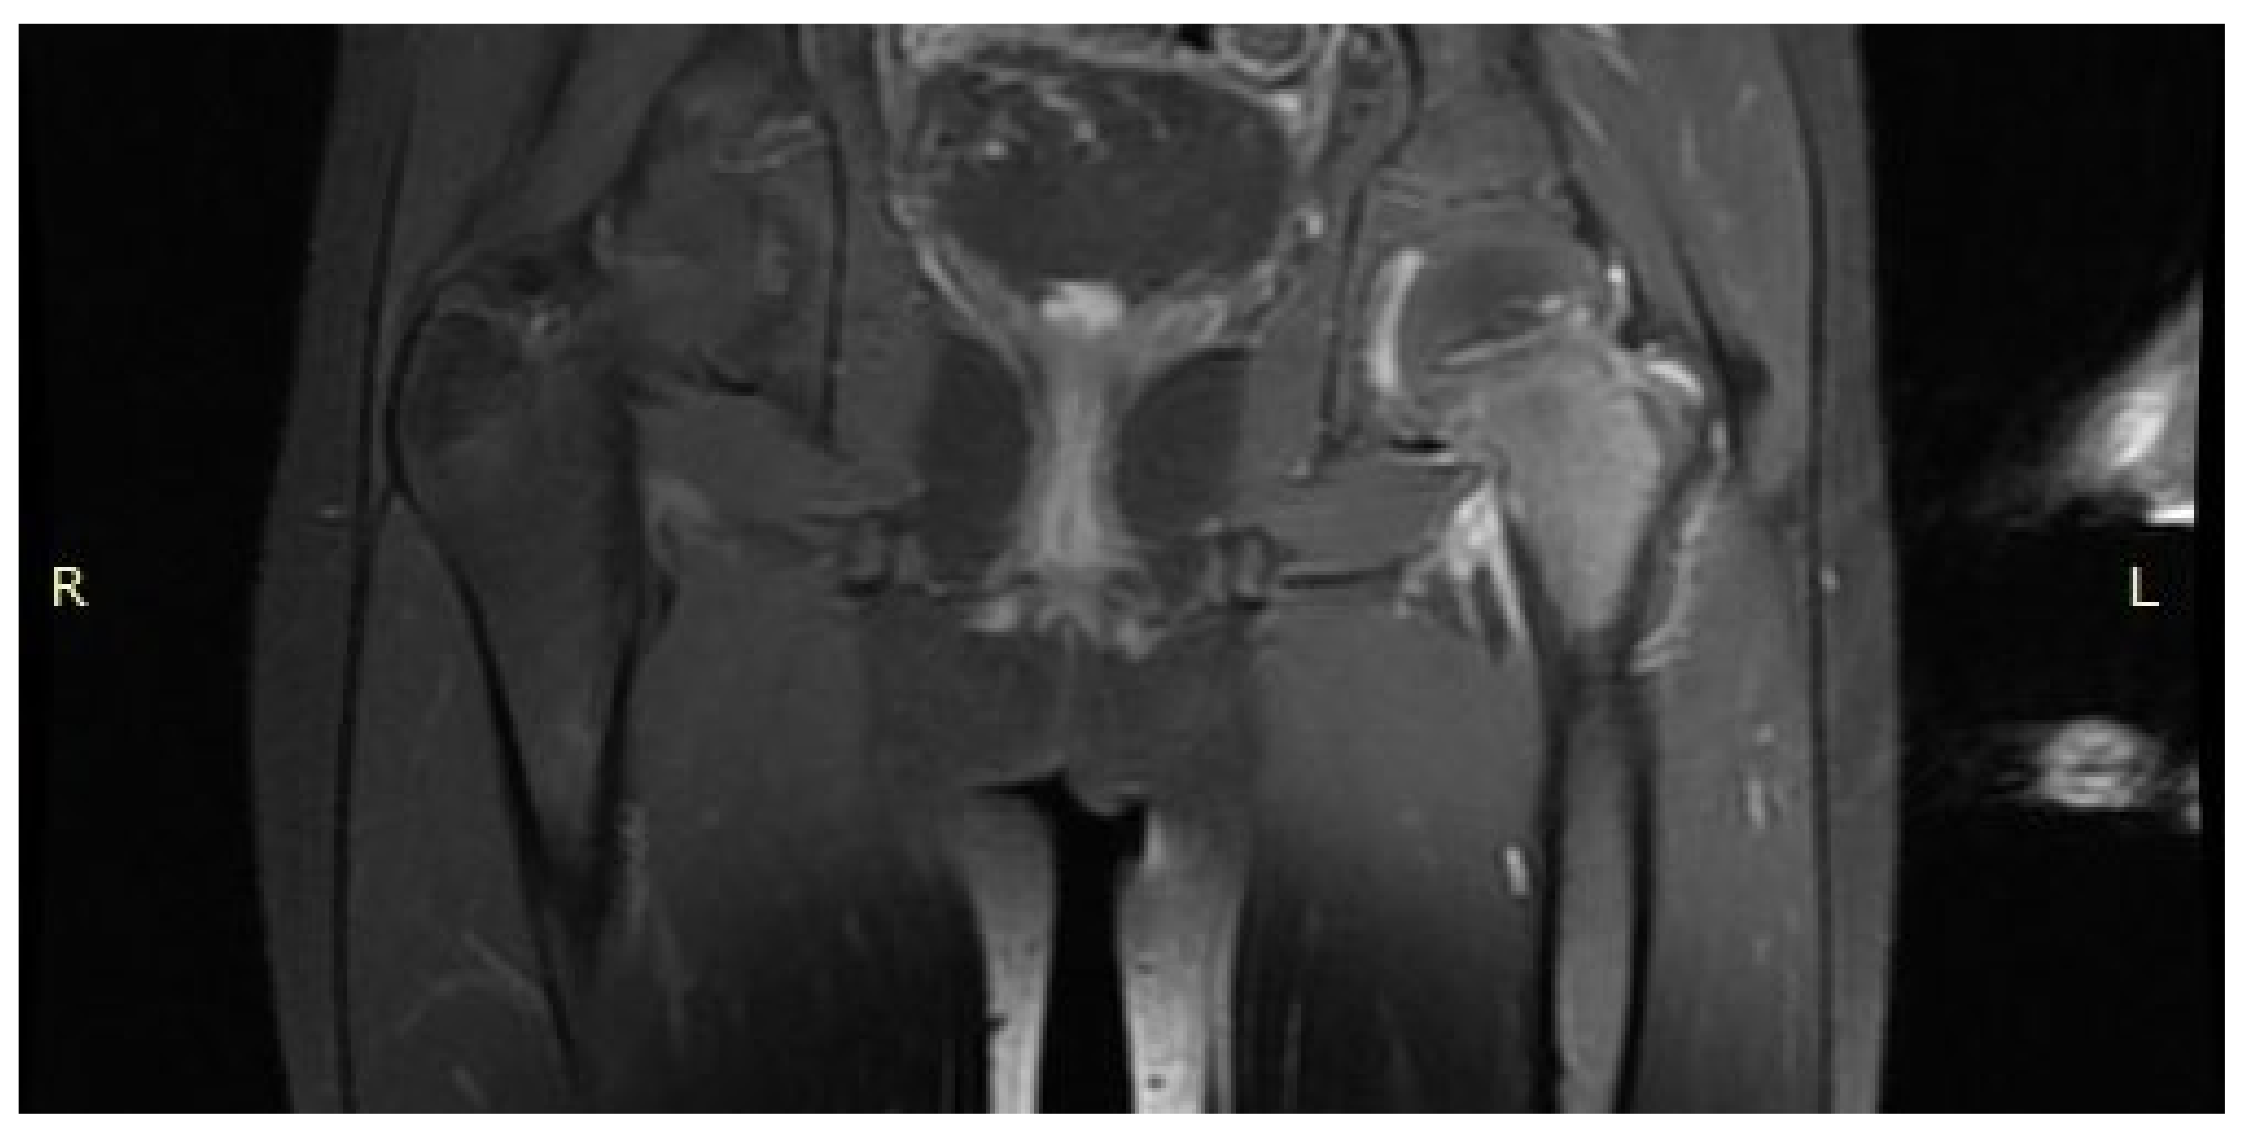

3.1. Case 1: OO Masking as Femoroacetabular Impingement (FAI)

3.2. Case 2: Example of an Incorrect Therapeutic Path of OO

3.6. Case 6: OO Masking as Chronic Hip Arthritis